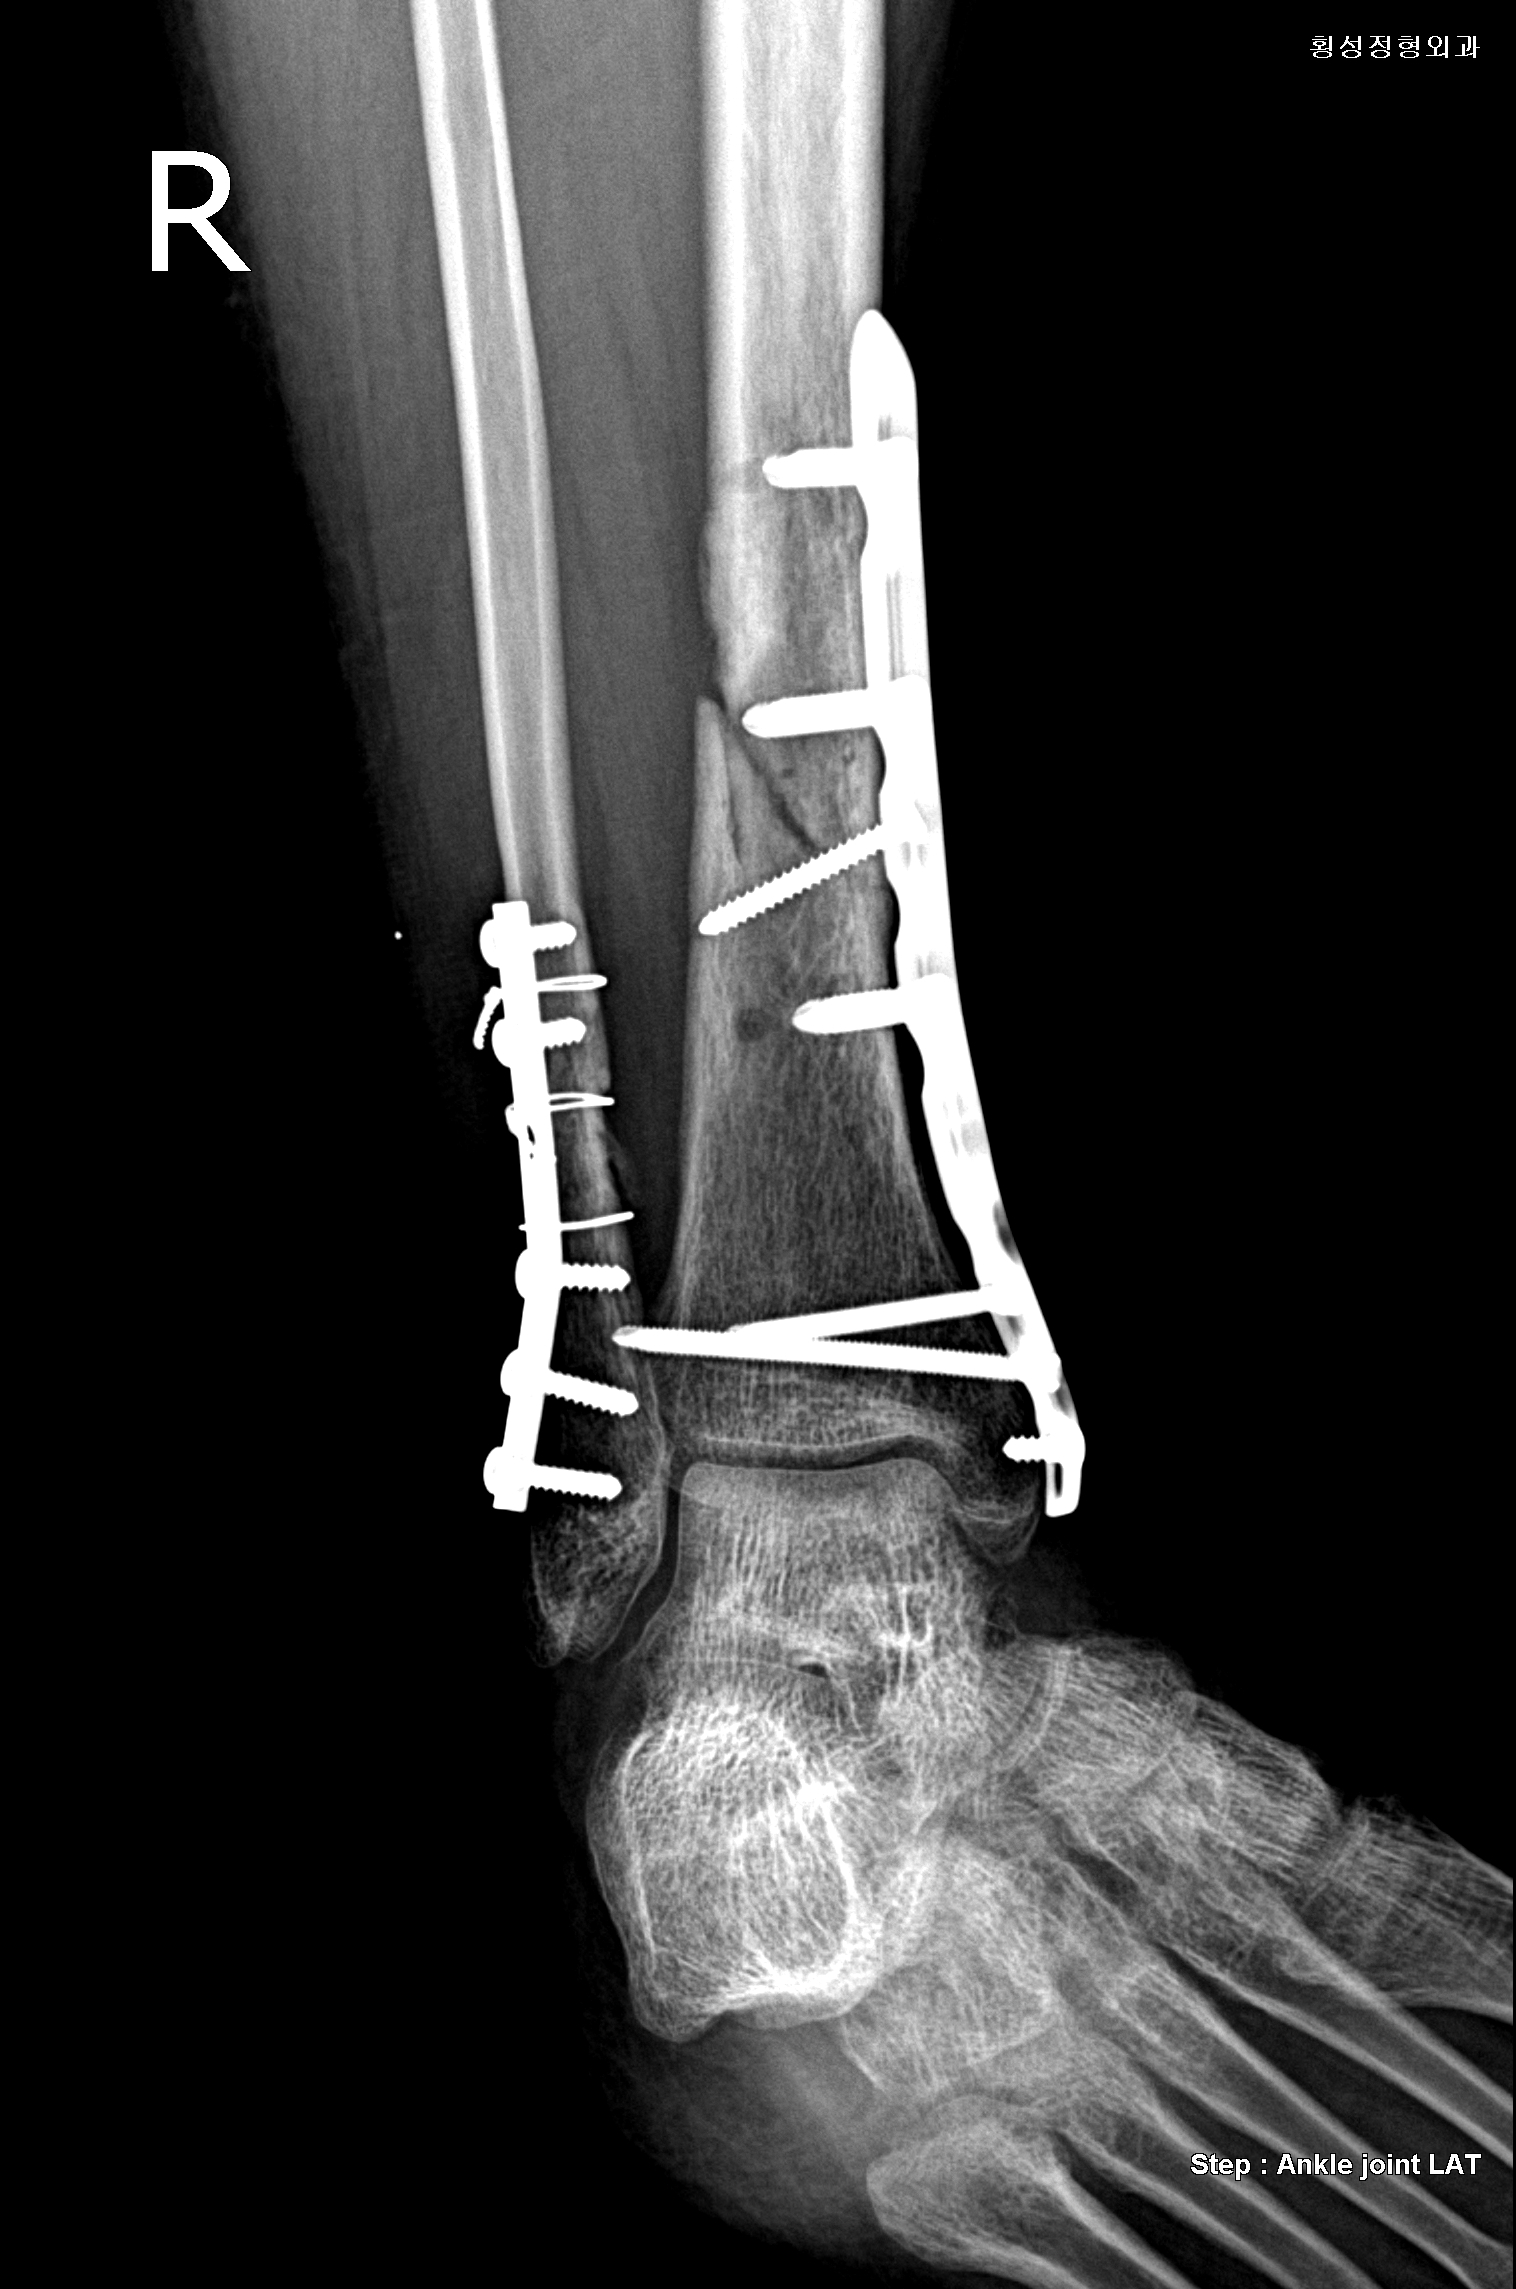

뼈세포 주입술 하기 전에 마지막으로 재활병원가서 엑스레이 사진을 찍어봤습니다...

그런데 3개월동안 차도가 없다고 하더니 오늘 가서 찍은 사진은 희미하게 뼈진이 보인다고 합니다.(저는 잘 안보이는데) 인제 목발 안 짚고 천천히 걸어도 된다고 하시더군요...

그래서 의사 선생님한테 뼈세포 주입술에 대해 말씀드렸더니 본인의 판단으로는 진행이 안되는 상태는 아니라서 좀 더 지켜보고 싶다고

하시더군요...근데 제가 넘 힘들다고 말씀드렸더니 본인이 힘들면 시술을 하는 것이 좋다고 합니다....

우선 제가 생활하기가 좀 힘들고 빨리 낫고 싶어서 그러는데...그리고 현재 상태가 정확하게 어느 정도인지 알고 싶습니다.

정말로 붙을 가능성이 있는건지...선생님의 의견을 듣고 싶습니다...(다음주 월요일에 뼈세포 주입술 관련 상담을 받으러 의정부에 갈려고 하는데 선생님한테 진료가 가능한지요?/